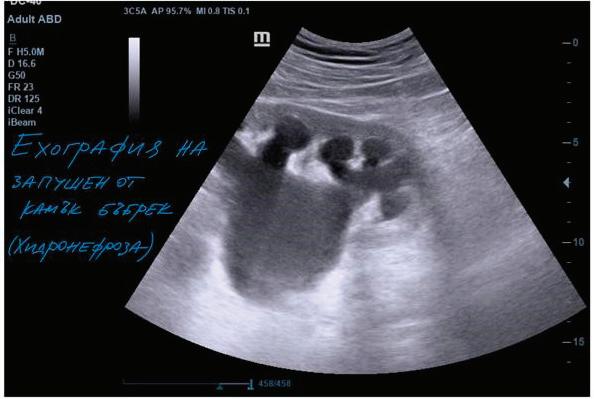

66 БЪБРЕЧНО-КАМЕННА БОЛЕСТЕТИОЛОГИЯ, ЧЕСТОТА, ЛЕЧЕНИЕ И ПРОФИЛАКТИКА В. Василев, Н. Димитров